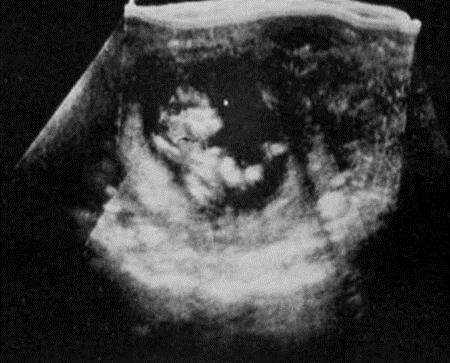

While the invention of the stethoscope was influential in discovering movement before quickening, ultrasound, first used in diagnostic medicine in 1956, helped scientists realise that pregnancy starts earlier than believed This began the transition from historical to modern perceptions